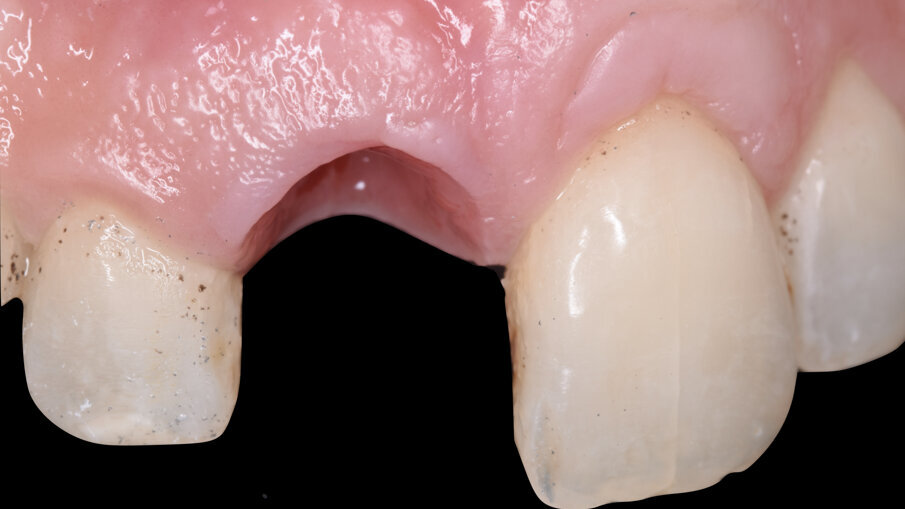

La paziente è stata dimessa con terapia farmacologica di supporto e a due settimane si è proceduto alla rimozione delle suture riassorbibili e i controlli clinici sono stati eseguiti poi a 1 mese, 3 mesi e 5 mesi. Al termine della fase di maturazione dei tessuti (5 mesi) (Fig. 7) si è evidenziato come da un punto di vista clinico siano stati mantenuti i volumi sul piano verticale (addirittura più coronali di circa 2 mm rispetto al centrale contro-laterale 2.1) e sul piano trasversale vestibolo palatale, e inoltre il nuovo esame CBCT evidenziava la ricostruzione della parete ossea vestibolare (Fig. 8).

Dopo un full fotografico completo, l’analisi dei fattori di rischio estetici, clinici e radiografici ha identificato la necessità di procedere all’estrazione dell’1.1 e sua sostituzione con una riabilitazione implantoprotesica secondo un timing e un protocollo di post estrattivo di tipo 3: estrazione, gestione dei volumi ossei e gengivali e a distanza di 4/5 mesi posizionamento dell’impianto3.